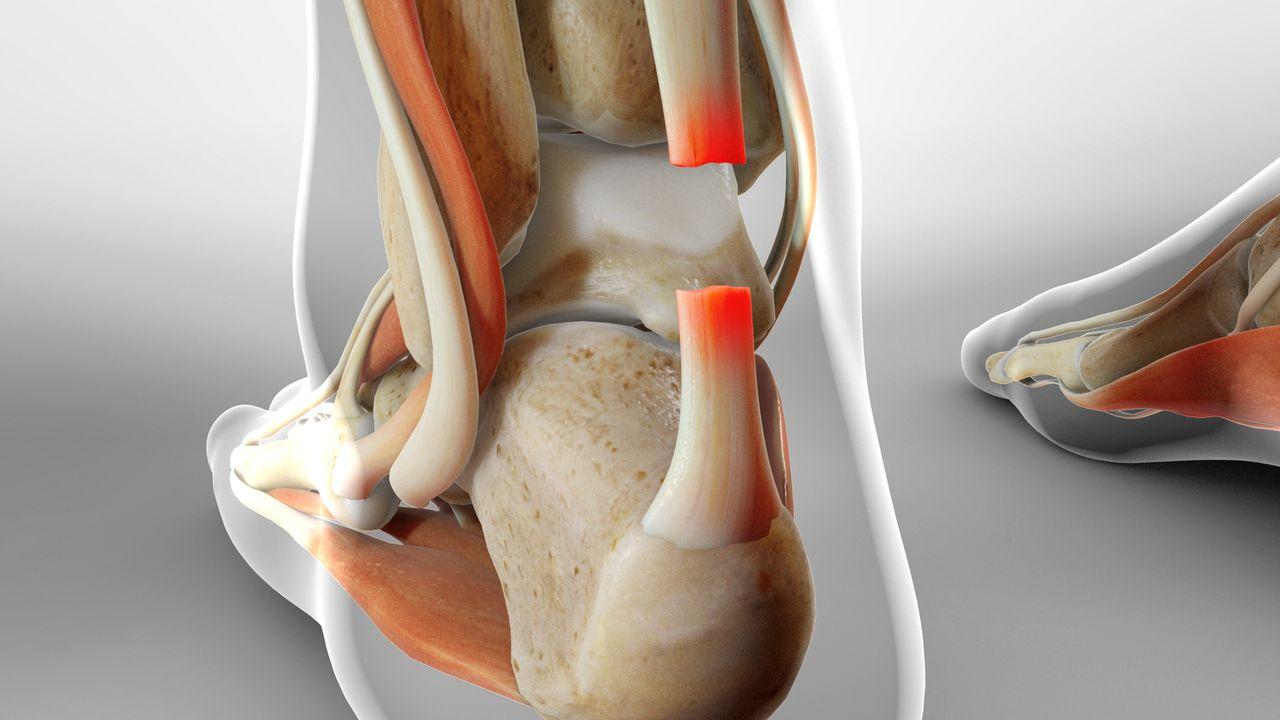

跟腱斷裂的處理方式有兩種,周禮智醫師說明,一為物理治療,因跟腱位於皮下,血液循環不佳,治療多以伸展運動及超音波、電療為主,若是治療效果不佳時,可考慮震波或血小板濃縮液注射(PRP),進而達到止痛及治療效果;另一方式為手術,將斷裂的肌腱接上去,嚴重時需要另外補肌腱,來強化跟腱,術後以石膏、特製的腳踝護具或支架固定3個月。